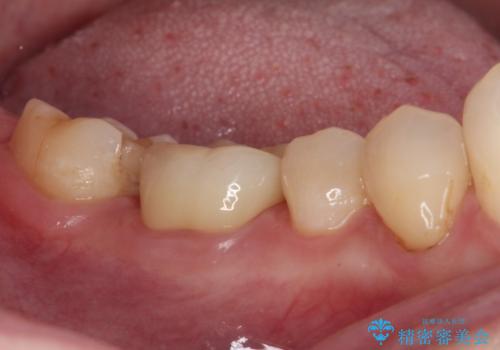

3歯別々に治療したクラウンは、どれも未治療の前歯を異なる色調で、口元が縞模様の印象でした。

更に、土台やフレームの金属色により、歯肉ラインが黒ずんでしまっていました。

色調を統一するために、未治療の1歯もクラウンを装着するかどうか悩んでいらっしゃいましたが、結果としては治療せずに4前歯の色調を合わせることができました。